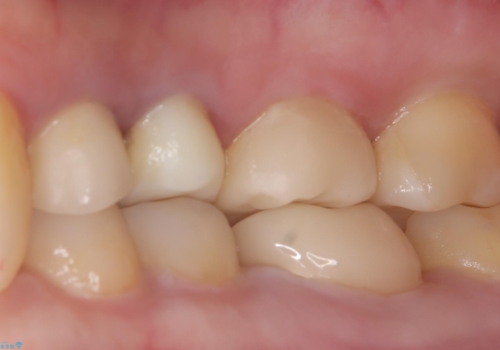

よく見ると歯冠部に咬合面から近心側にのびるヒビ(クラックライン)が入っているのが見えます。

「噛むと歯が鈍く痛む」を主訴に来院されました。

各種検査を行い、咬合面にヒビ(クラック)を認めました。

元々咬合面にレジンインレーが入っており、近心歯質が薄くなっていたことや、食いしばるクセを持っていることも、ヒビが入った要因の一つと考えられます。